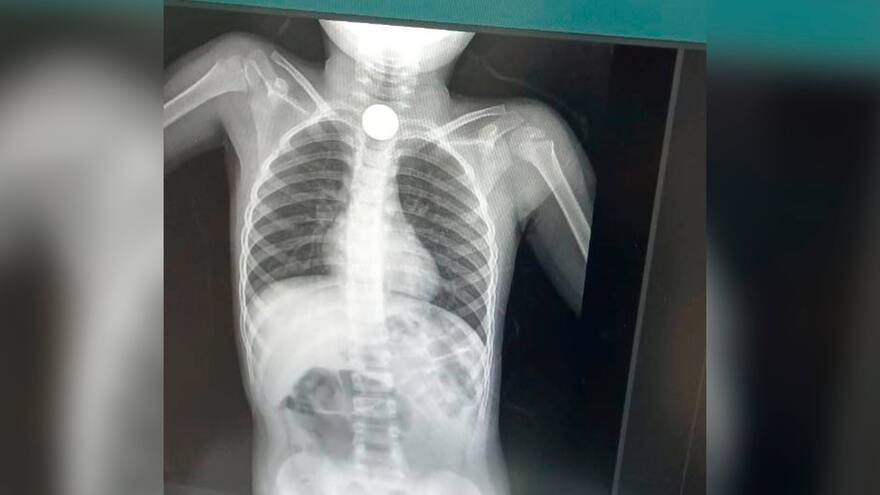

Niño se tragó monedas